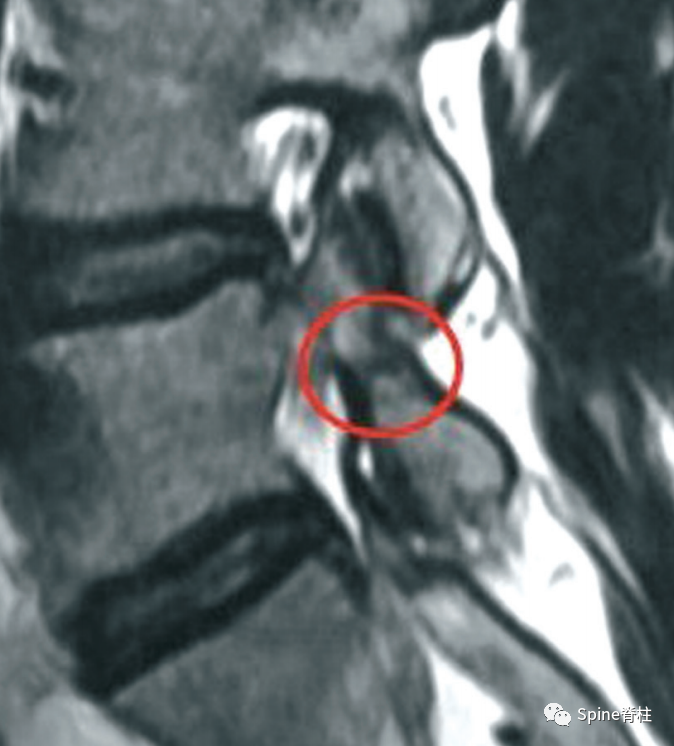

MRI提示的峡部裂(红圈)

有研究发现磁共振上椎弓根出现T2高信号改变是青少年和儿童峡部裂的早期诊断征象。同时,存在椎弓根高信号改变也是保守治疗后能达到骨性愈合的良好预测指标(也就是说存在T2椎弓根右高信号改变的峡部裂患者,其峡部裂经保守治疗愈合的可能性大)

Sairyo教授研究发现磁共振上椎弓根出现T2高信号改变是青少年和儿童峡部裂的早期诊断征象。同时,存在椎弓根高信号改变也是保守治疗后能达到骨性愈合的良好预测指标(也就是说存在T2椎弓根右高信号改变的峡部裂患者,其峡部裂经保守治疗愈合的可能性大)。